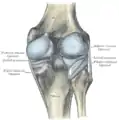

Lateral and posterior aspects of right knee

The knee is a modified hinge joint, a type of synovial joint, which is composed of three functional compartments: the patellofemoral articulation, consisting of the patella, or "kneecap", and the patellar groove on the front of the femur through which it slides; and the medial and lateral tibiofemoral articulations linking the femur, or thigh bone, with the tibia, the main bone of the lower leg.[6] The joint is bathed in synovial fluid which is contained inside the synovial membrane called the joint capsule. The posterolateral corner of the knee is an area that has recently been the subject of renewed scrutiny and research.[7]